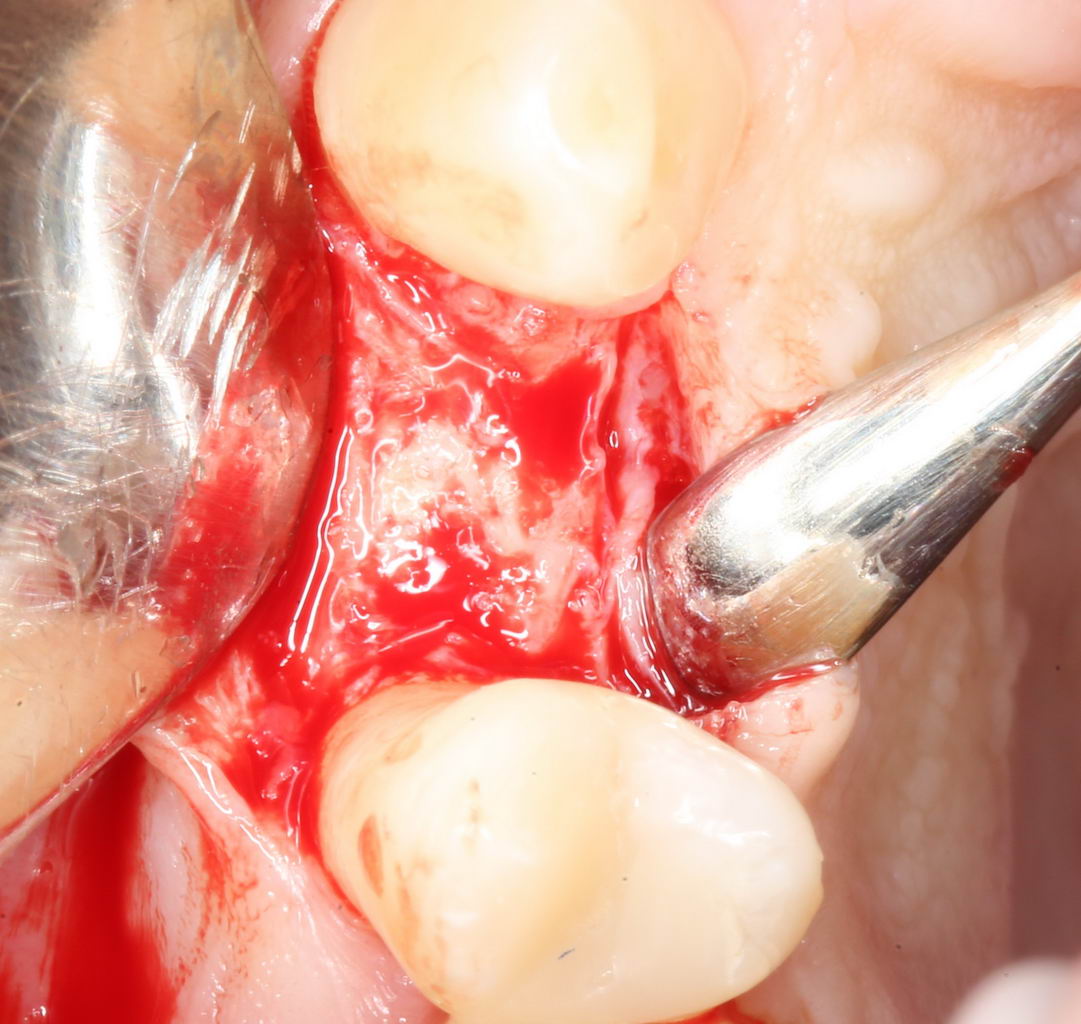

Для окончательного формирования десневого контура, осталось только наложить швы.

Наложение швов.

Помните, в самом начале операции мы планировали наложение швов с учётом будущего вестибулярного смещения лоскута? Так вот, теперь у нас есть возможность не просто сместить, но и зафиксировать вестибулярный лоскут. Делается это, так сказать, с подворотом края снаружи:

Обратите снимание, что альвеолярный отросток в этой области стал более объемным. Этого удалось добиться без всяких остеопластических операций или гингивопластики, путём простого перемещения тканей.